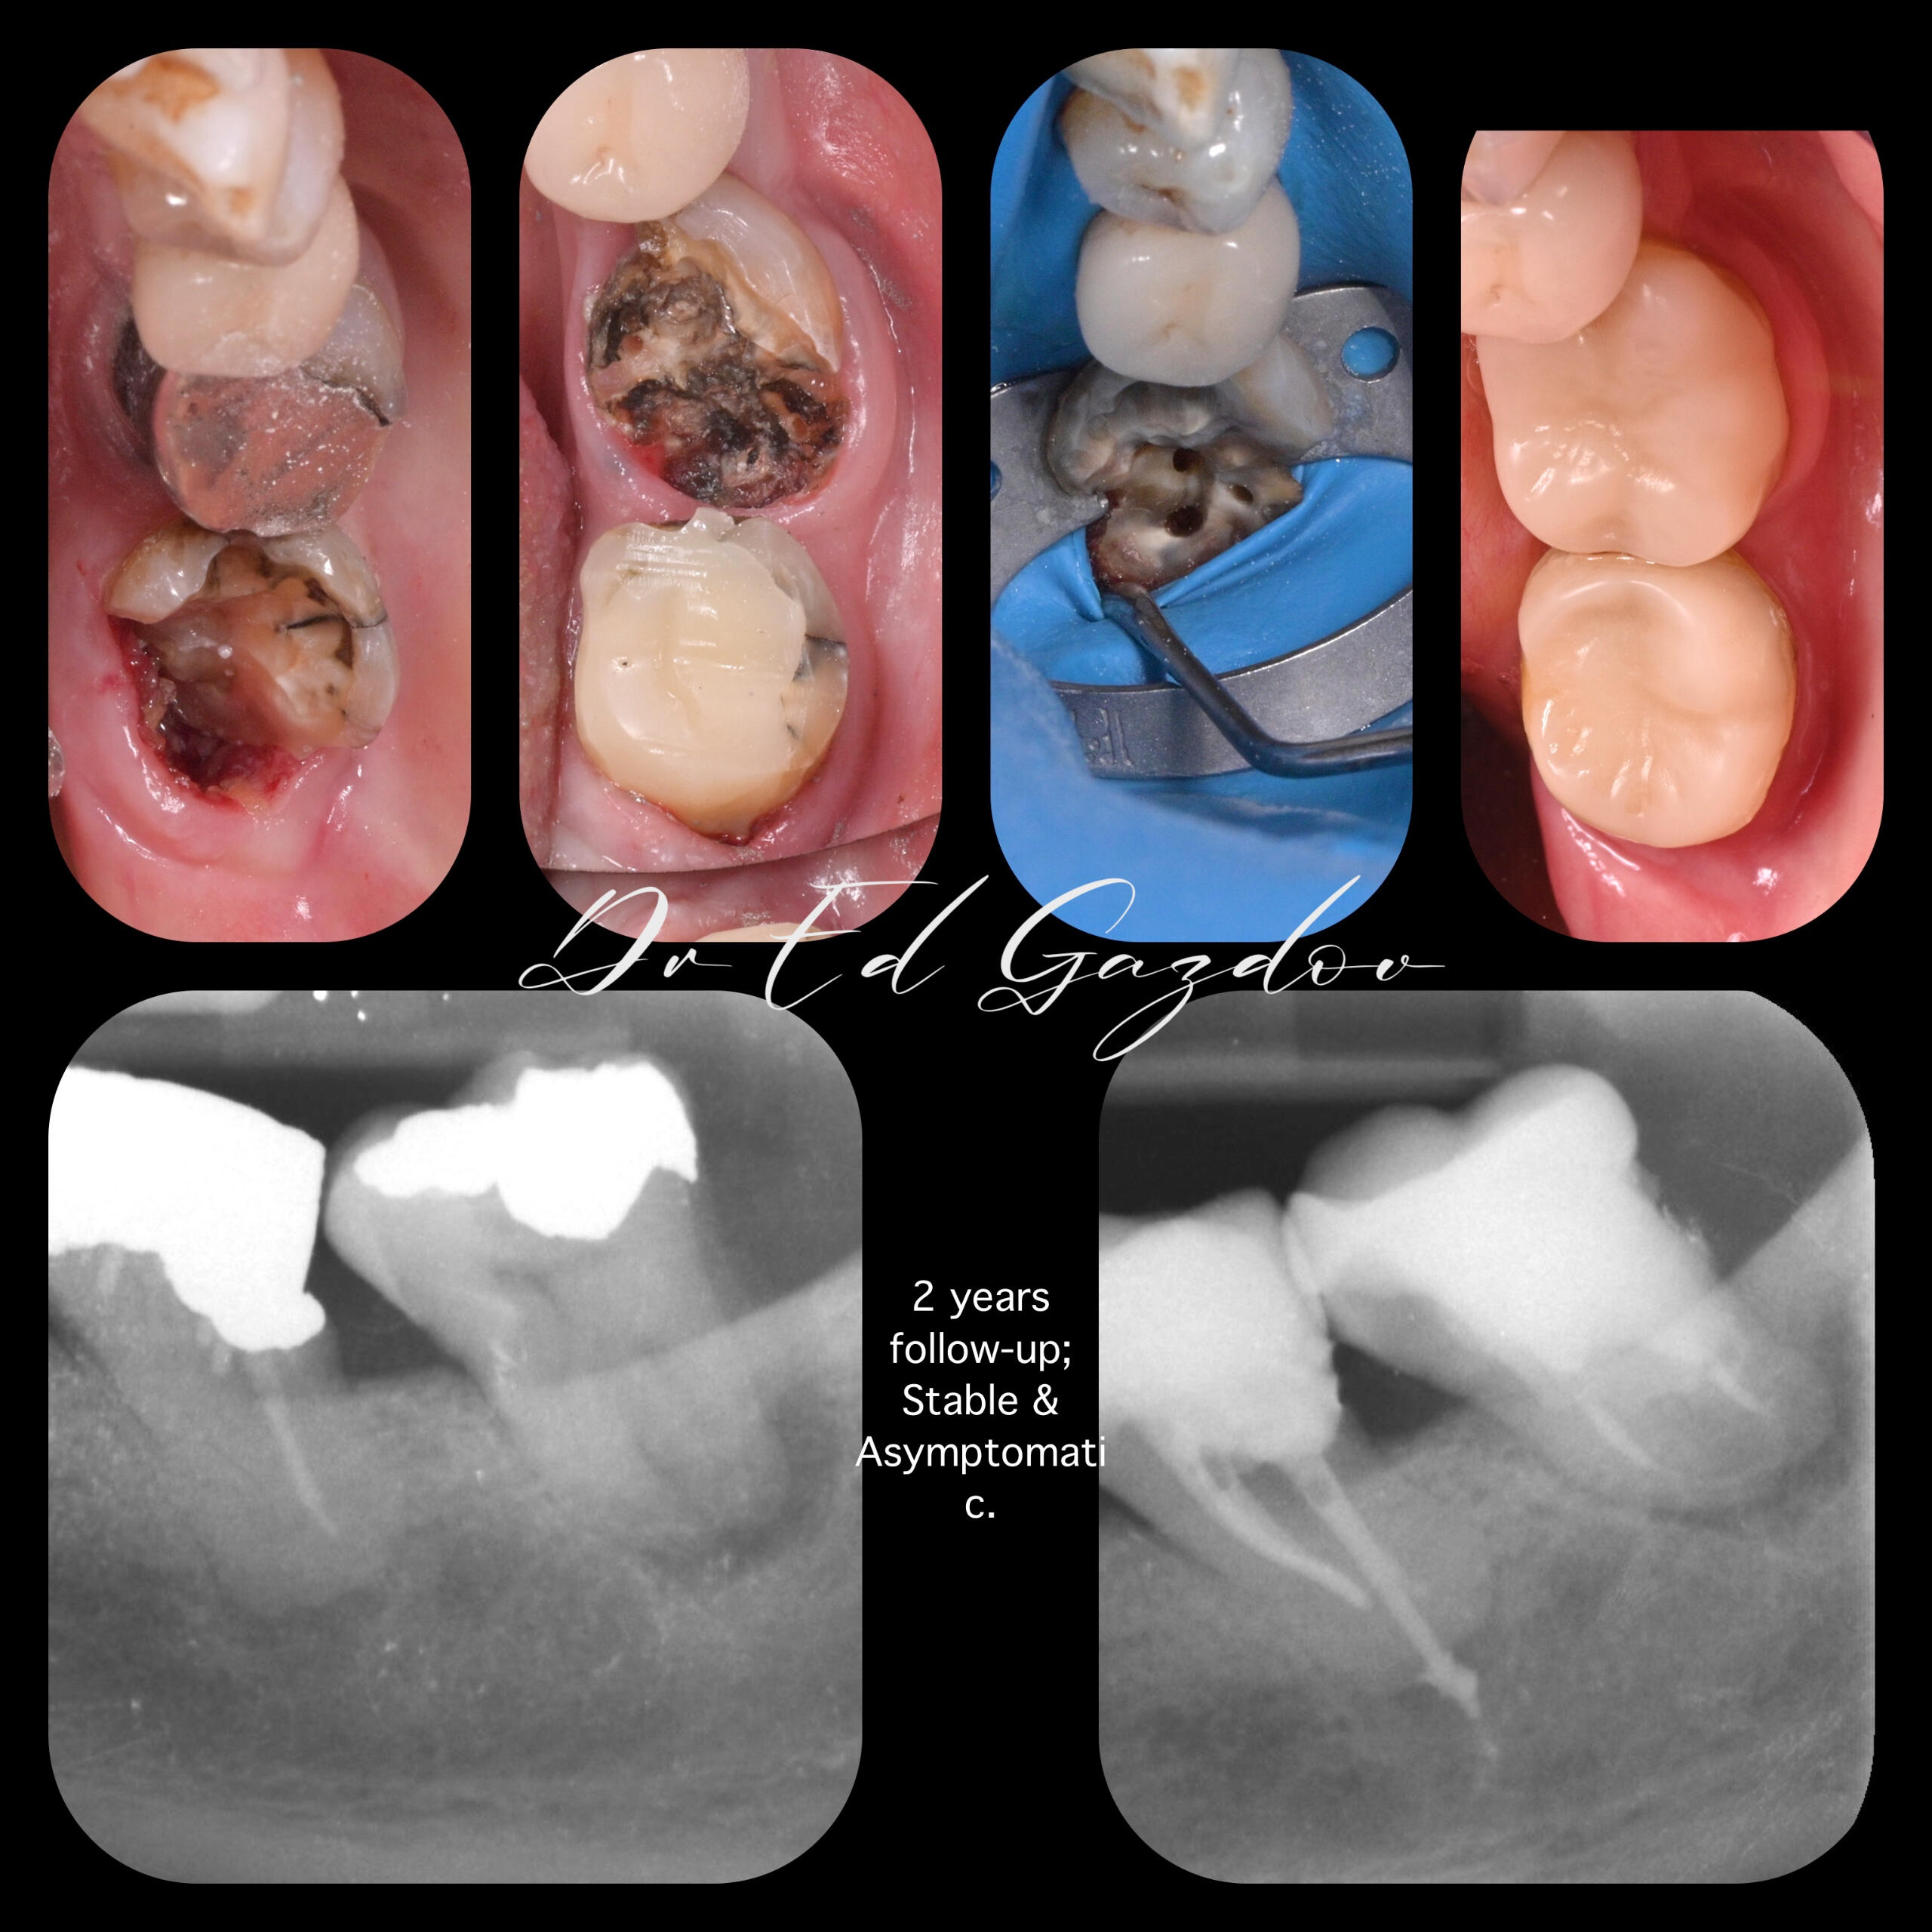

• Запазване на силно увредени зъби

• Импланти с незабавно или водено поставяне – според случая и Вашите предпочитания• Фасети, корони и мостове с минимално изпиляване и естествена визия• Пълна трансформация на усмивката, планирани дигитално и изпълнени с внимание към естетиката• Хирургично вадене на зъби, включително трудни или инфектирани случаи• Директни фотополимерни възстановявания – бързо и щадящо решение при отчупвания и леки корекции• CEREC корони и инлеи, изработени и поставени на място, в рамките на часове• Прелекуване на стари канали, корони и мостовеРаботим под увеличение, използваме rubberdam, модерни дигитални технологии и най-висок клас материали.Обясняваме ясно какво правим и защо — за да се чувствате спокойни, уверени и информирани на всяка стъпка от лечението.